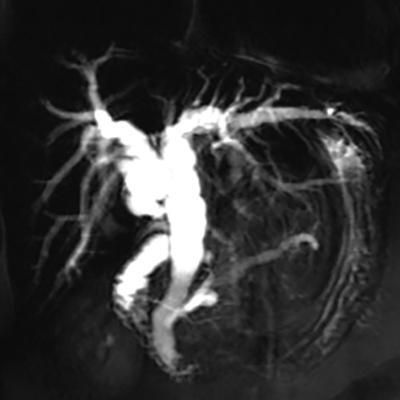

Shrinivas B. Desai, Ritu K. Kashikar, Shreya Shukla Radiological signs are classical and distinctive abnormalities characteristic of a disease. These can be seen on any imaging modality. Resemblance to commonly seen objects and patterns form the basis of radiological signs. The aim is to help the reader associate, understand and memorize these pathologies with the aid of signs. Various signs pertinent to hepatobiliary system are described in the chapter. Described on MRI when liver lesion shows a peripheral rim of high T2 signal intensity with the centre of the lesion appearing isointense to the background of noncirrhotic liver on T2WI mimicking an atoll. It is considered a characteristic sign of an inflammatory hepatic adenoma (image) but is only seen in about one-third of cases Extrinsic smooth impression over medial aspect of duodenum along its posteroinferior aspect, seen in pancreatic head pathologies like carcinoma. This sign is seen in pancreatic adenocarcinoma Presence of a persistently hyperattenuating dot within a lesion on arterial and portal venous CT. This corresponds with peripheral nodular enhancement seen on dynamic MR. Presence of bright dot suggests that the lesion is a hemangioma and helps in ruling out metastasis Ultrasound appearance of multiple cystic spaces or lesions that has been used to describe the appearance of an intraductal papillary mucinous neoplasm of the pancreas. Seen on contrast CT in portal hypertension. The appearance is based on resemblance to Medusa from Greek mythology. Dilated engorged paraumbilical veins radiating across umbilicus to join systemic veins is seen. This sign is seen in Caroli’s disease on contrast CT. Enhancing dots within dilated intrahepatic bile ducts represent portal radicles. Caroli’s disease Irregularly dilated pancreatic duct with multiple strictures and intervening dilatation with associated dilated side ductules resemble multiple lakes supplied by a single territory. Best seen in MRCP images. Chronic pancreatitis It is a finding on MRI and CT and is best seen on MRI T2-weighted and postcontrast T1-weighted sequences. Small necrotic/purulent areas in the pyogenic abscess ‘cluster’ together and then coalesce into a larger necrotic/purulent areas, eventually becoming a larger septated abscess cavity. At the periphery of these clusters: Associated with pyogenic hepatic abscesses and can help differentiate pyogenic abscesses from other types of liver lesions Abrupt termination of gas within the proximal colon at the level of radiological splenic flexure. The inflammatory exudates in pancreatitis extend to the phrenicocolic ligament giving rise to this sign Seen on grey scale ultrasound as a reverberation artifact when small calcific or highly reflective objects are imaged. The colour comet-tail artifact is an ultrasonographic sign seen in a number of situations when colour Doppler scanning is performed. This sign occurs in cases of traumatic right-sided diaphragmatic rupture with resultant partial herniation of liver through the defect. Separation of the herniated liver from its intra-abdominal component is via a small constriction at the level of diaphragm resembling a cottage loaf. Cottage loaf is a particular shape of bread in which larger and smaller roughly spherical balls are squashed together. Traumatic right-sided diaphragmatic rupture with resultant partial herniation of liver Bile eccentrically outlines luminal stone, creating a low attenuation crescent. Best seen on MRCP images. Choledocholithiasis Dilatation of both pancreatic duct and CBD is referred to as the double duct sign. Positive double duct sign suggests the diagnosis of carcinoma of the head of the pancreas and ampullary tumours and is hence considered ominous. Occasionally the sign may be seen in impacted gallstone in the distal duct. This feature is seen in patients with liver abscess on contrast-enhanced CT. A double, inner hyperattenuating and outer hypoattenuating rim is seen surrounding the hypodense abscess. The inner hyperattenuating rim corresponds to the enhancing abscess membrane, while the outer rim corresponds to the edema of the surrounding liver which appears hypodense and may show delayed enhancement. Liver abscess A positive duct penetrating sign is when a mass is penetrated by an unobstructed pancreatic duct; this makes focal pancreatitis the most likely cause rather than pancreatic carcinoma. This sign is best appreciated on MRCP (or ERCP). A radiographic sign that can be useful in differentiating between focal pancreatitis (inflammatory pancreatic mass) from pancreatic carcinoma. The duct-penetrating sign on MRCP is more helpful in differentiating between these two entities than a delayed enhancement pattern on CT or MRI It occurs when there is both limy bile and a gallstone in the common bile duct. The linear vertical radiopaque bile forms the line of the exclamation mark (i.e. !), whilst a more distal calculus forms the ‘dot’ at the end of the exclamation mark. Pathognomonic imaging sign of the rare diagnosis of limy bile on plain abdominal radiography Nonenhancing ruptured lesion with peripheral rim enhancement showing discontinuity from the rest of the liver and protruding from the liver surface is called the enucleation sign. Ruptured HCC Enlargement of the pericholecystic space. One of the signs of liver cirrhosis Can be seen on technetium 99m sulphur colloid scans of the liver and spleen, as well as CT studies. It occurs as a focal area of increased radiopharmaceutical uptake in the medial segment of the left hepatic lobe (segment IV) occurring as a result of SVC obstruction and portosystemic venous shunting between the superior vena cava and the left portal vein via the internal thoracic and paraumbilical veins. The equivalent of this sign may also be seen on contrast-enhanced CT scans as a hypervascular region. Budd–Chiari syndrome causes the hot spot sign in the caudate lobe

1) Atoll sign